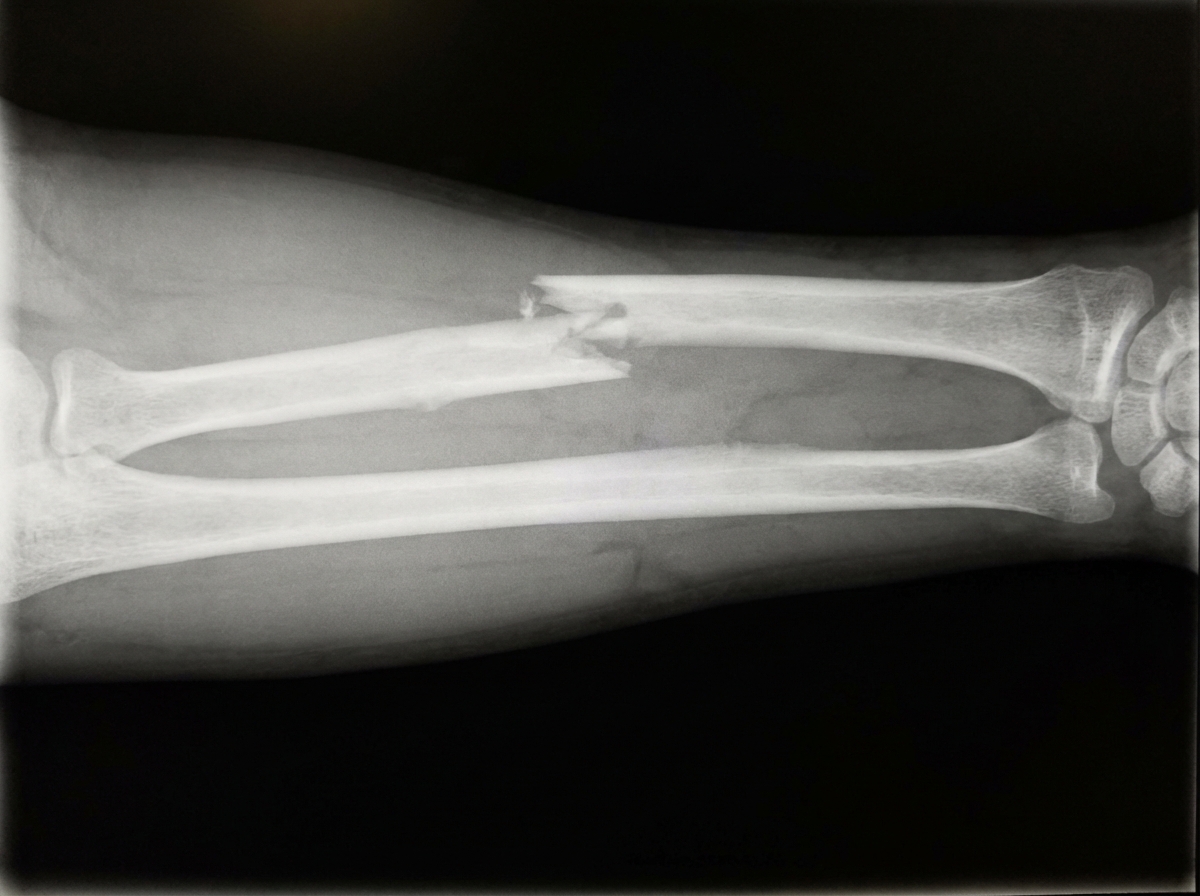

What is the management for the depicted condition?

Explanation: ***Internal fixation with compression plating*** - **Both-bone forearm fractures** require anatomical reduction to restore the **radial bow** and maintain proper **radioulnar relationship** for forearm rotation. - **Dynamic compression plating** provides rigid fixation allowing early mobilization and optimal functional outcomes in displaced diaphyseal fractures. *Closed reduction* - Inadequate for **displaced both-bone fractures** as it cannot maintain anatomical alignment and **radial bow**. - High risk of **loss of reduction** and malunion leading to **restricted forearm rotation** and functional impairment. *Cast immobilization* - Cannot maintain reduction in **unstable diaphyseal fractures** of both radius and ulna. - Risk of **compartment syndrome** from swelling within the cast and poor functional outcomes due to malunion. *External fixation* - Reserved for **open fractures** with severe soft tissue damage or **infected nonunions**. - Does not provide adequate **rotational control** and anatomical restoration required for optimal forearm function.